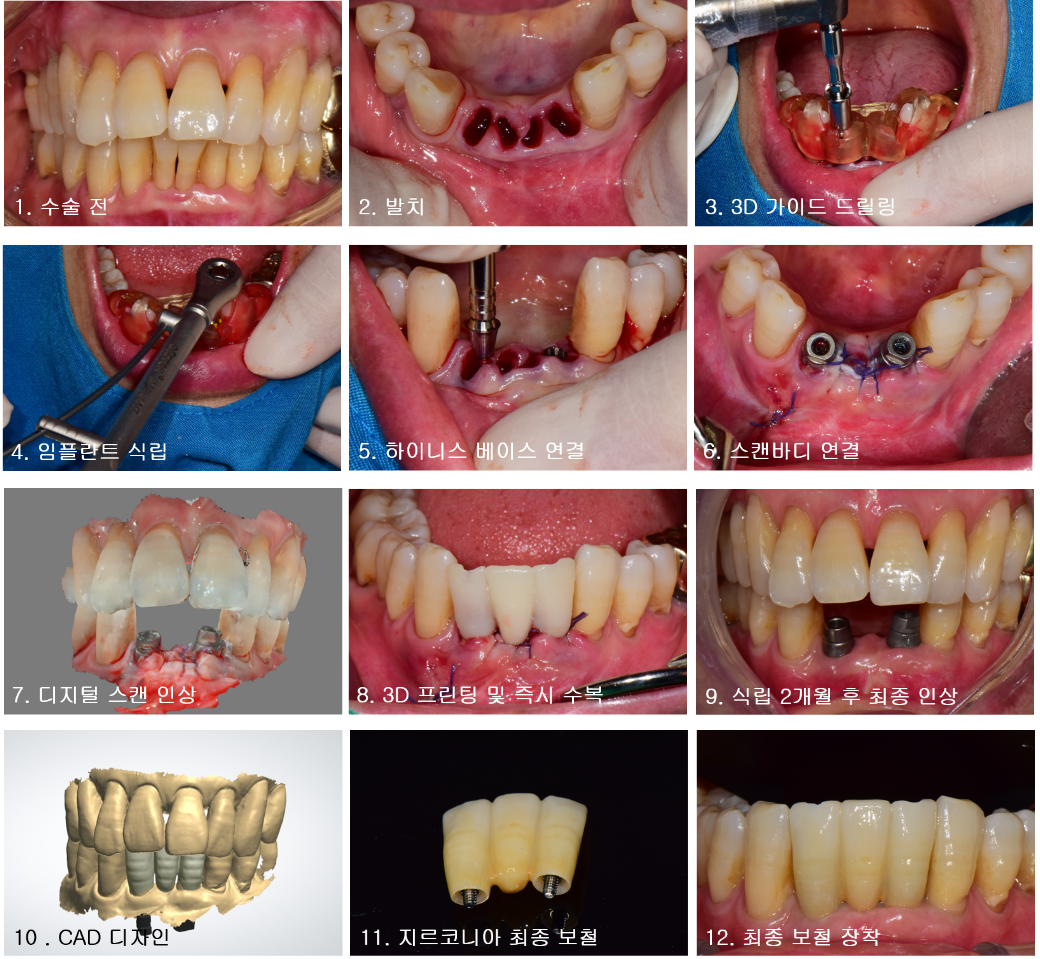

위쪽 증례에서 보듯이 하이니스 보철 시스템을 활용하여 Immediate implant placement 및 Immediateloading을 성공적으로 시행하였다. 임플란트 식립 직후 디지털 스캔인상을 채득하고 CAD 작업 후 3D 프린터로 즉시 수복물을 제작하였다.

수술 당일 임플란트 보철을 장착할 수 있으므로 심미성과 기능적인 측면에서 환자와 술자 모두 만족할 수 있었다.

하이니스 보철 시스템은 앞서 언급한 교합력 분산효과 외에도 스크루 유지형 보철이므로 임시 수복물의 형태 수정이 매우 용이하고 잔여시멘트에 의한 염증 발생을 우려할 필요가 없다.

이를 통해 심미적인 연조직 재형성과 안정적인 골치유가 가능하므로 최종보철 제작을 위한 최적의 환경을 구축할 수 있다.

Immediateloading 시 임상의 편리성을 위해 간편한 보철제작은 필수적 요건이라 생각된다.

하이니스 보철 시스템은 customized abutment 제작없이 디자인 파일의 3D 프린팅이나 PMMA 밀링만으로도 임시보철물 제작이 가능하므로 기존의 방식보다 Immediate/Early loading 편리하게 사용할 수 있다.